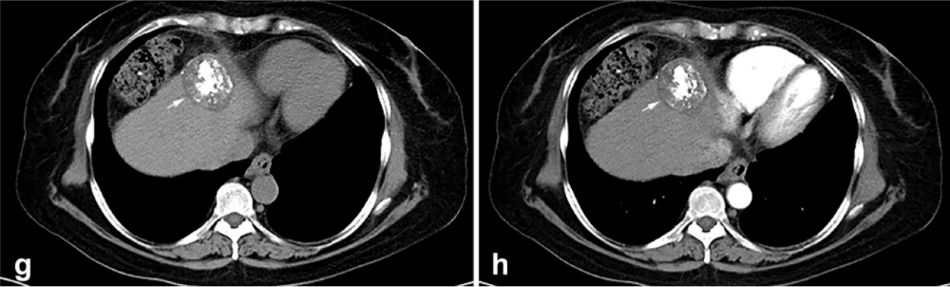

② 冷凍消融后 1 個月患者的增強(qiáng) CT 顯示HCC獲得緩解。

③ 總生存曲線和局部腫瘤進(jìn)展曲線:冷凍消融后中位生存時間為 27.3 個月,中位局部腫瘤進(jìn)展時間為 20.9 個月。